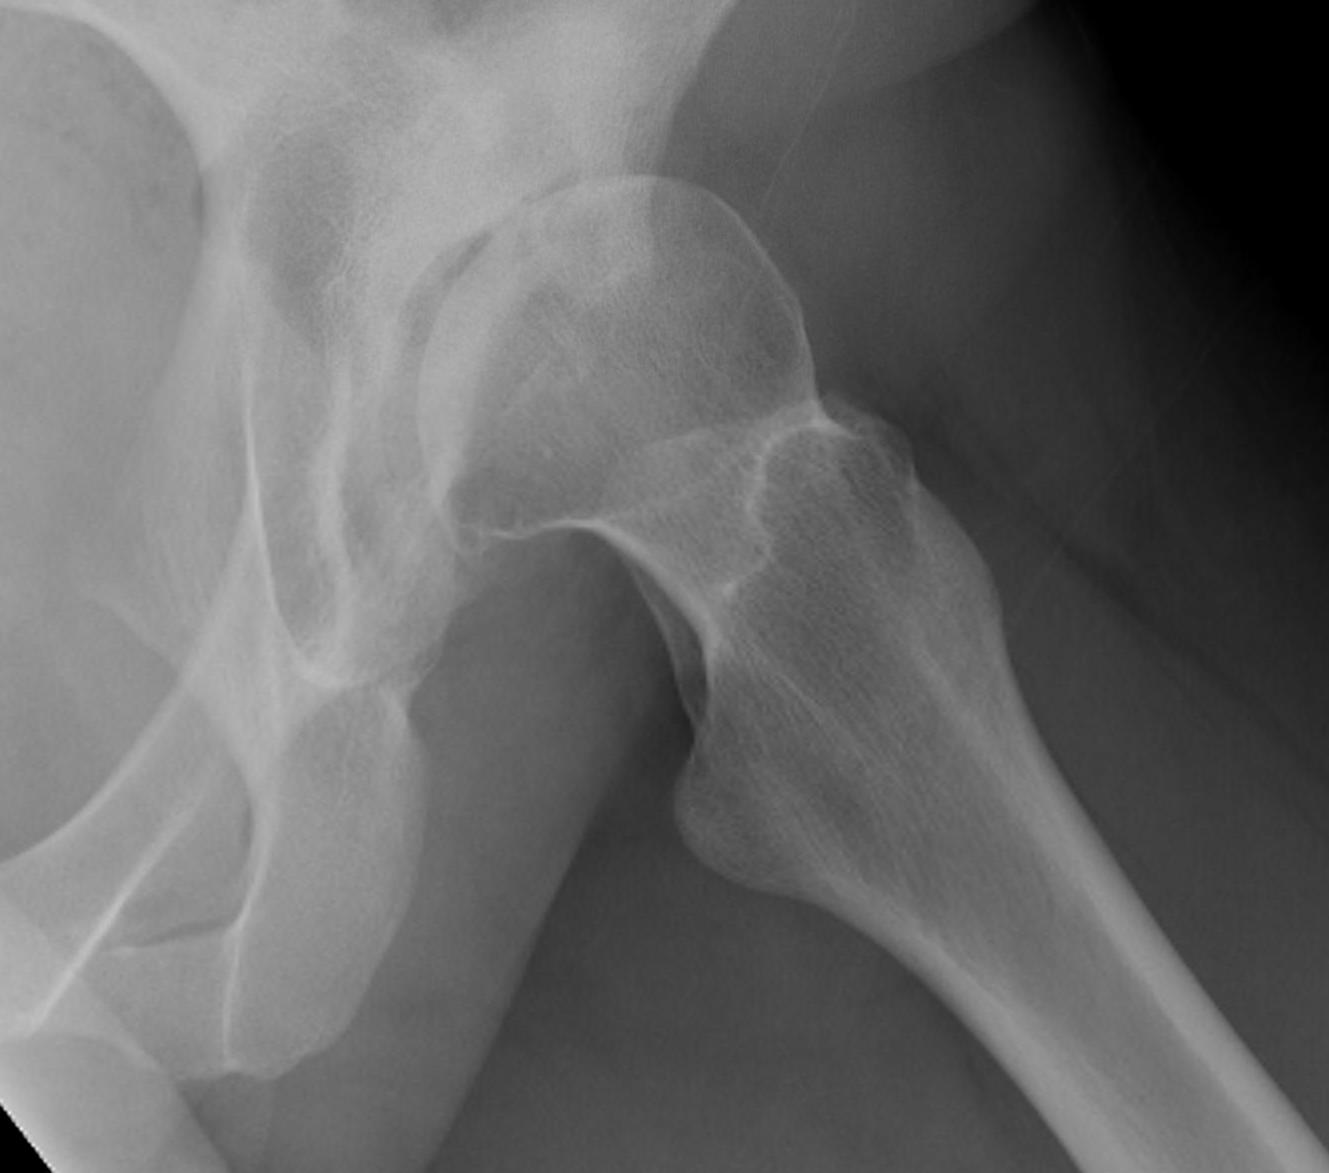

Crowe II

Crowe III